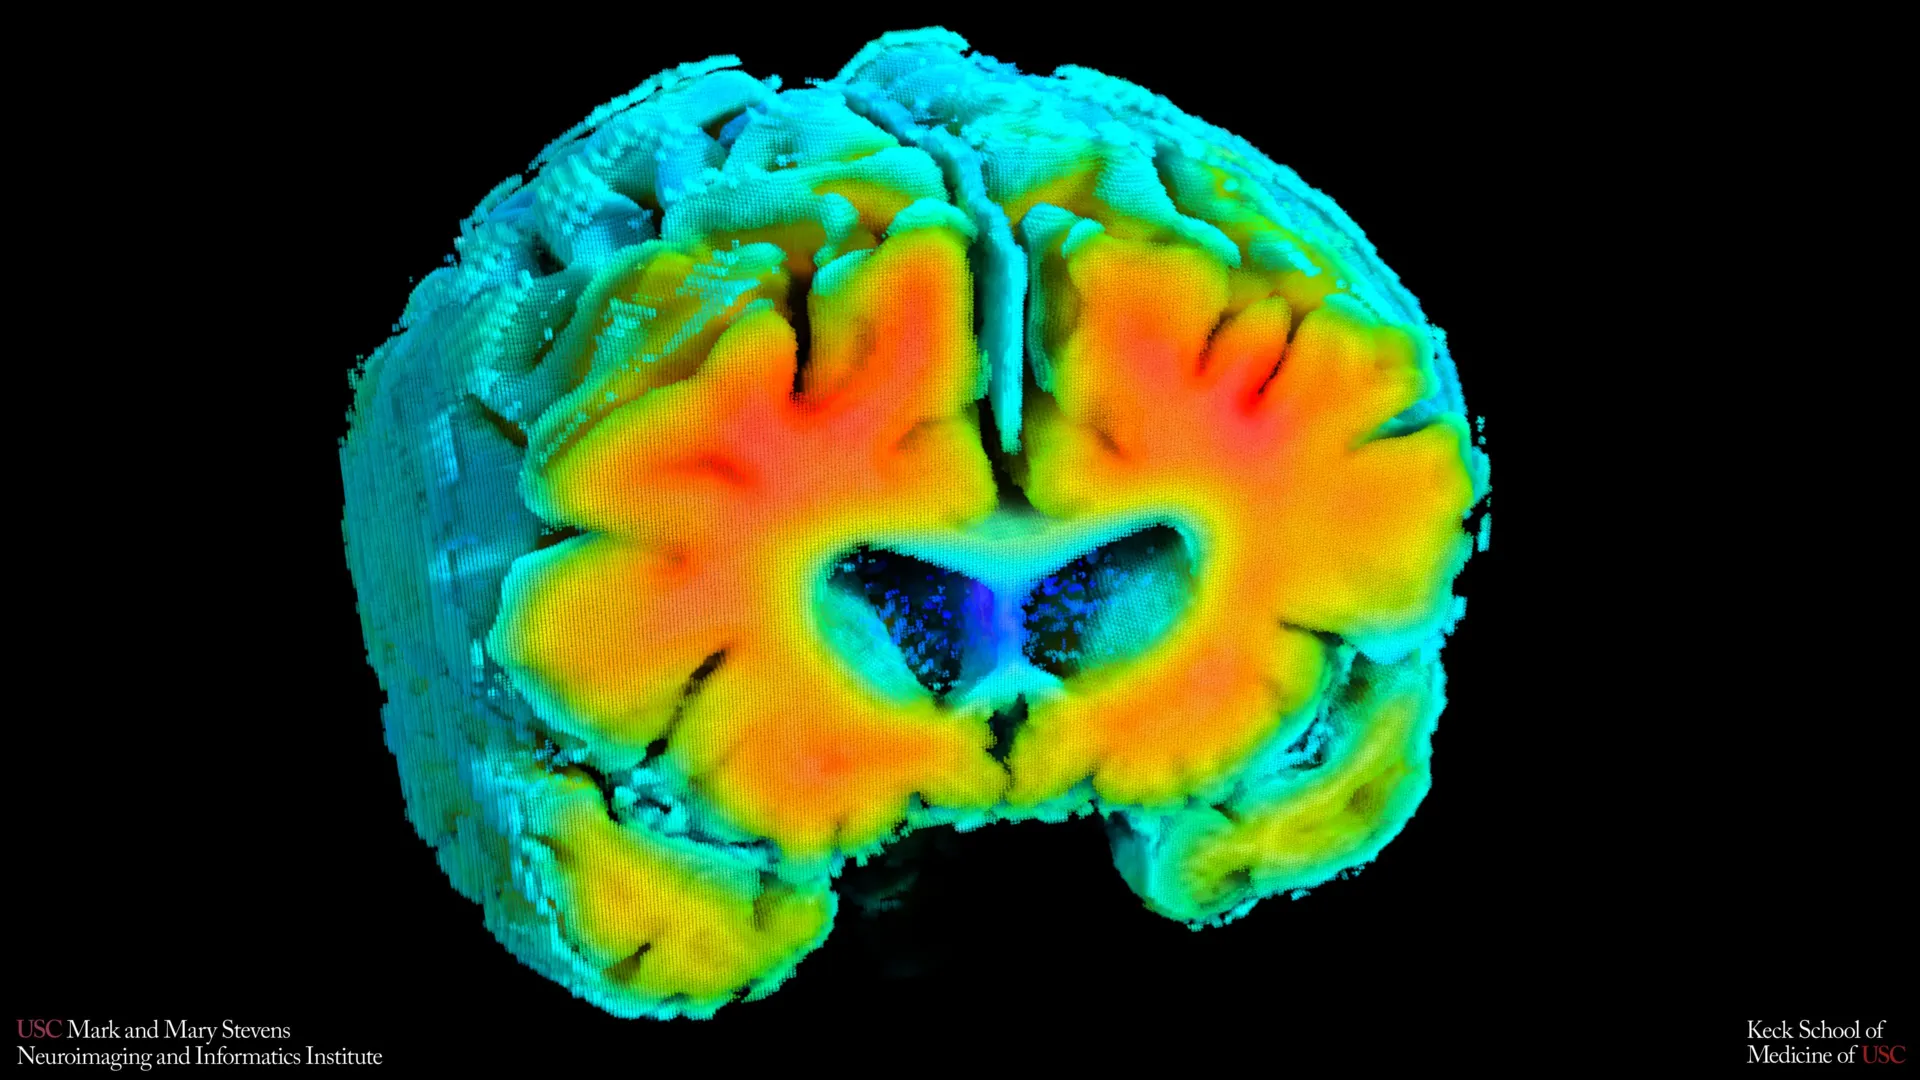

New research emerging from the Mark and Mary Stevens Neuroimaging and Informatics Institute (Stevens INI) at the Keck School of Medicine of USC is shedding light on potentially overlooked early indicators of Alzheimer’s disease. The study, published in the esteemed journal Alzheimer’s and Dementia: The Journal of the Alzheimer’s Association, posits that subtle alterations in how blood circulates within the brain and how brain cells receive vital oxygen may be intricately linked to an individual’s risk of developing this devastating neurodegenerative condition. This groundbreaking work suggests that simple, noninvasive measurements could pave the way for earlier identification of individuals at risk, potentially even before the onset of noticeable cognitive decline.

The research team meticulously examined a cohort of older adults, comprising both individuals with and without diagnosed cognitive impairment. Their findings revealed a compelling correlation: straightforward, noninvasive assessments of brain blood flow and oxygen levels were demonstrably associated with well-established hallmarks of Alzheimer’s disease. These include the accumulation of amyloid plaques, protein deposits widely believed to play a significant role in the disease’s pathology, and the shrinkage of the hippocampus, a brain region critically involved in memory formation and retrieval. The implications of these findings are substantial, suggesting that the health and efficiency of the brain’s vascular system might exert a profound influence on the Alzheimer’s disease process from its nascent stages. This could offer a paradigm shift in how the disease is detected and potentially managed.

The study’s findings powerfully underscore the interconnectedness of vascular health and key Alzheimer’s disease markers. Participants whose cerebrovascular indicators more closely mirrored those observed in cognitively healthy individuals consistently exhibited lower levels of amyloid plaque buildup. Furthermore, these individuals tended to possess a larger hippocampal volume. Both of these characteristics – reduced amyloid burden and a more robust hippocampus – are independently associated with a lower risk of developing Alzheimer’s disease.

Dr. Meredith N. Braskie, the senior author of the study and an assistant professor of neurology at the Keck School of Medicine, commented on the significance of these findings. "These vascular measures are capturing something meaningful about brain health," Dr. Braskie explained. "They appear to align with what we see on MRI and PET scans that are commonly used to study Alzheimer’s disease, providing important information about how vascular health and standard brain measures of Alzheimer’s disease risk may be related." This suggests that these noninvasive vascular assessments could serve as a complementary or even an early surrogate marker for changes typically detected by more expensive and resource-intensive imaging techniques.

The research also identified a distinct pattern among individuals already diagnosed with mild cognitive impairment (MCI) or dementia. These participants, as a group, demonstrated weaker cerebrovascular function when compared to their cognitively normal counterparts. This observation provides robust support for the growing consensus that declining brain vessel health is not an independent comorbidity but rather an integral component of the broader Alzheimer’s disease continuum. It suggests a progressive deterioration that impacts both neuronal integrity and vascular support systems.

Echoing this sentiment, Dr. Arthur W. Toga, director of the Stevens INI, highlighted the broader implications for understanding Alzheimer’s. "These findings add to growing evidence that Alzheimer’s involves meaningful vascular contributions in addition to classic neurodegenerative changes," Dr. Toga remarked. "Understanding how blood flow and oxygen regulation interact with amyloid and brain structure opens new doors for early detection and potentially prevention." This integrated perspective is crucial for developing comprehensive therapeutic strategies that address the multifaceted nature of Alzheimer’s disease.